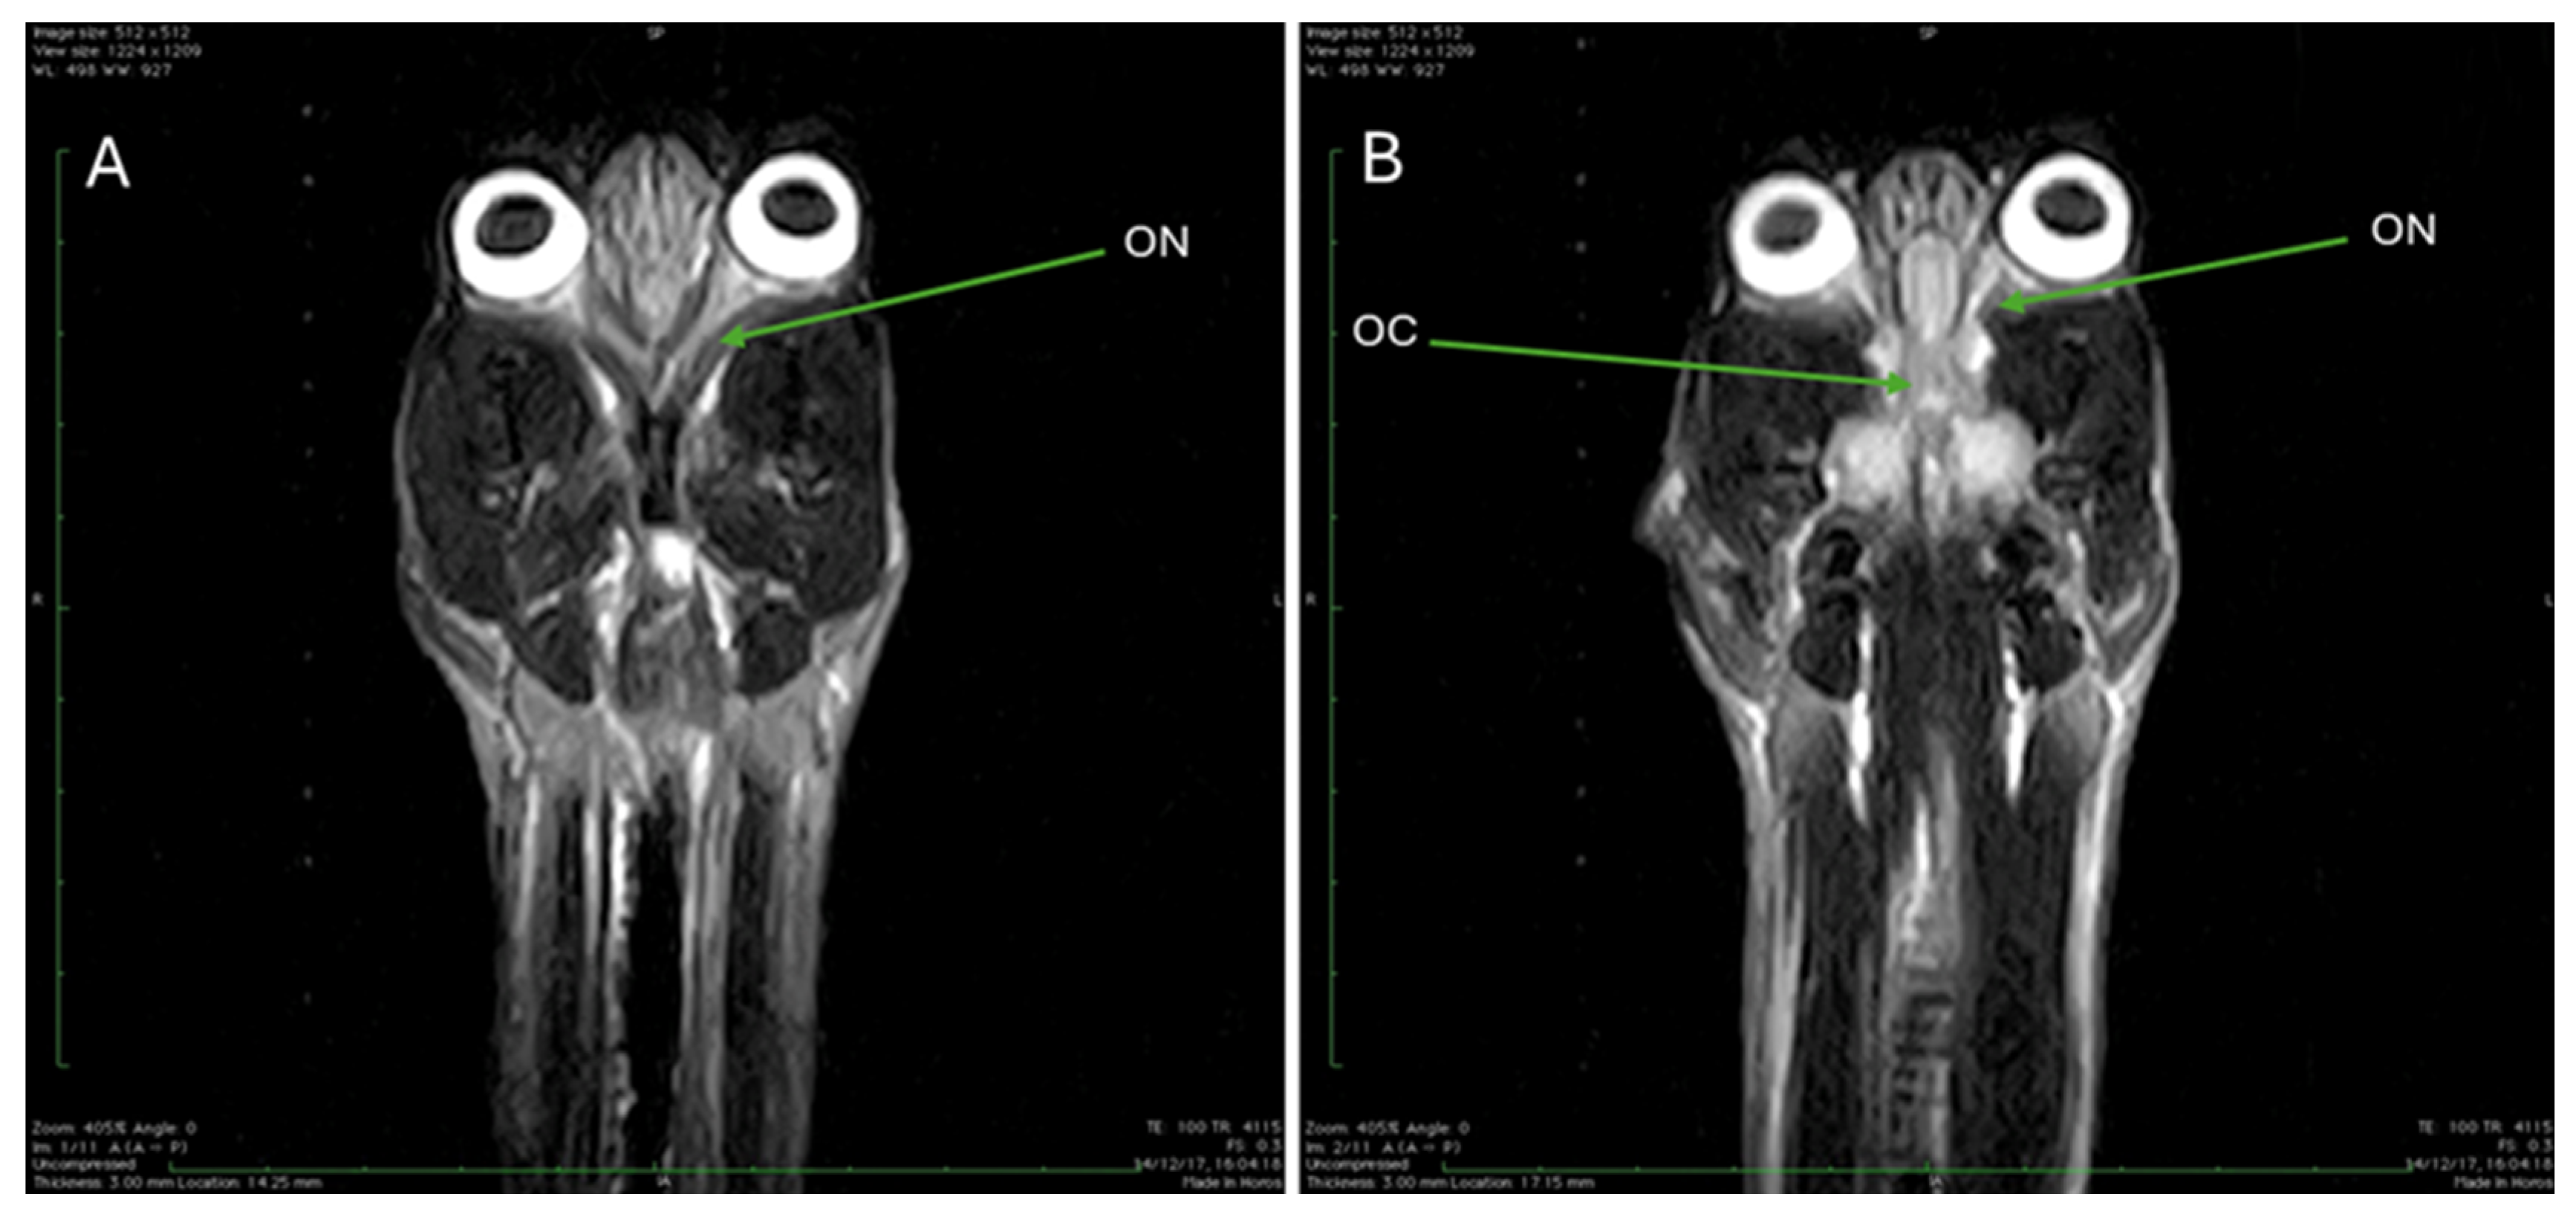

| ON | Optic nerve |

| OC | Optic chiasm |

3.3. Magnetic Resonance Imaging (MRI)